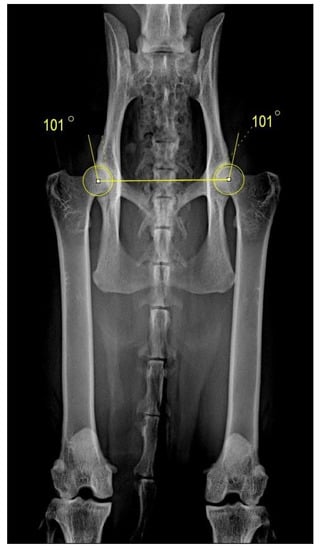

2. Materials and Methods